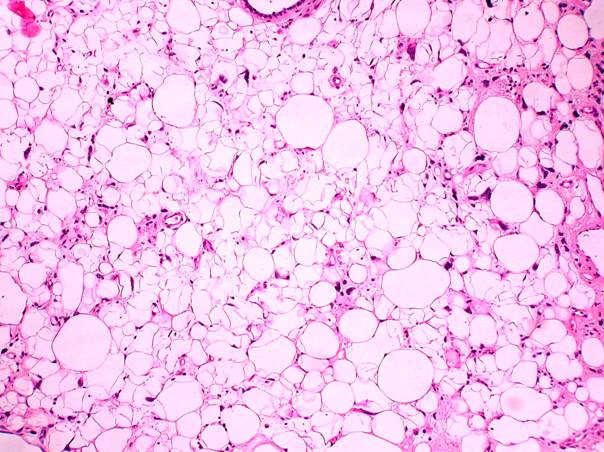

Microscopic examination of both specimens exhibited biphasic proliferation with pushing border, in which the stromal components displayed remarkable overgrowth (Fig.1). The stromal component was predominantly represented by adipose tissue with numerous hyperchromatic stromal cells and lipoblasts showing marked pleomorphism and atypia (Fig.2). Mitotic count in these areas was 2-3 per 10 high power fields. Highly atypical stromal cells were also intermingled with epithelial component. Only few foci with spindle cell stroma and leaf-like projections were seen (Fig.3). Malignant phyllodes tumor with heterologous liposarcomatous differentiation was diagnosed.

Fig 2

Stromal component with liposarcomatous differentiation (H&E, x 100)